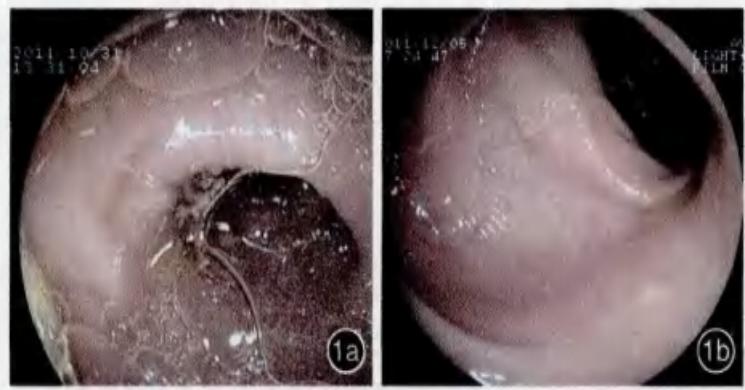

下图示:观察组及对照组肠道准备方法的肠道清洁度在结肠镜下的视野对比。

图2.1a:复方聚乙二醇电解质散肠道准备组结肠镜下视野

1b:硫酸镁联合酚酞片及ORS肠道准备组结肠镜下视野(图片来源于中华消化内镜杂志)